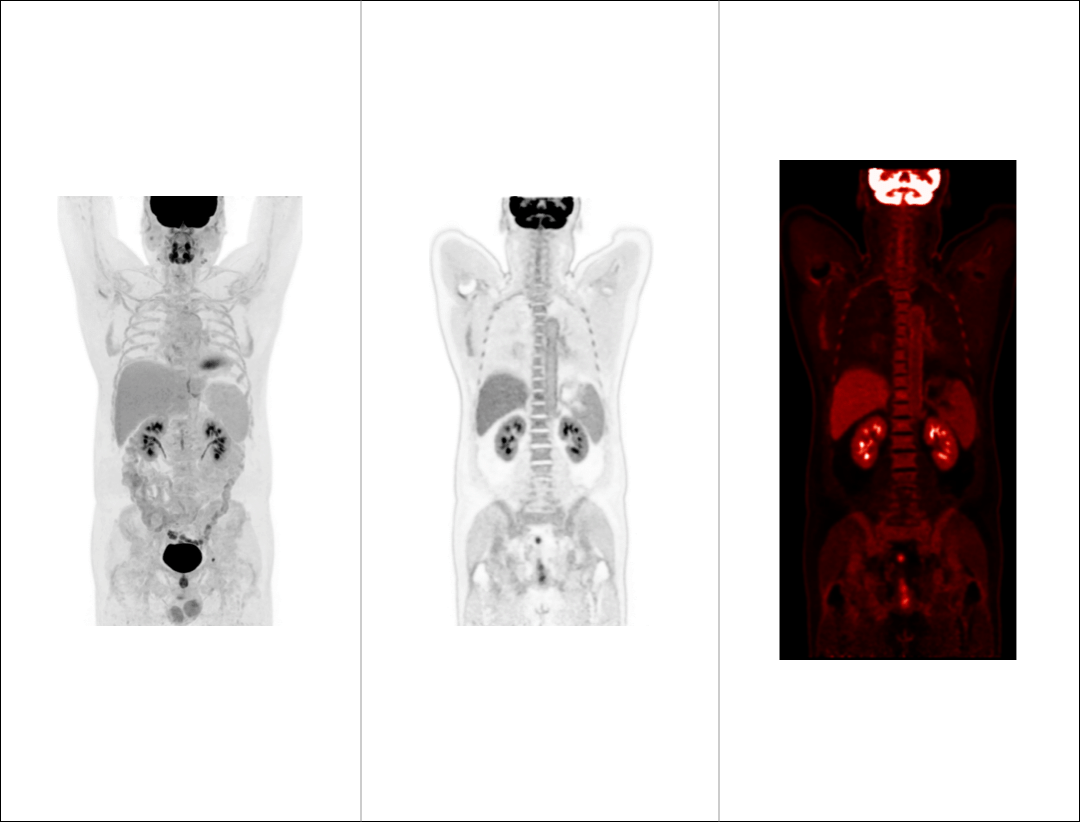

支持68Ga、 90Y、18F、82Rb、15O等不同半衰期、不同核素药物高清显像

68Ga-DOTA-NOC PET/CT 高清显像